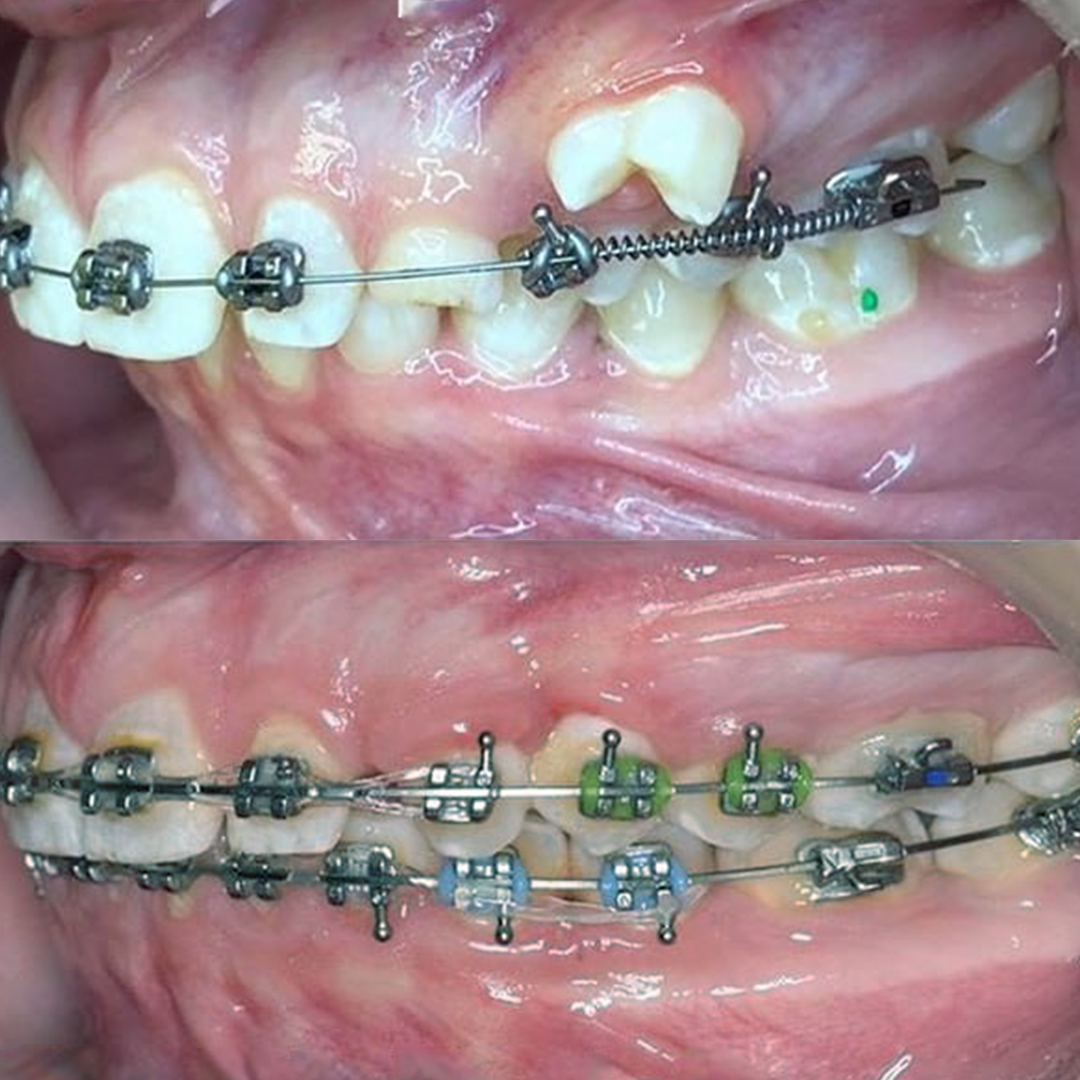

Результат коррекции металлической брекет-системой

Результат коррекции самолигирующей брекет-системой

Результат коррекции керамической брекет-системой